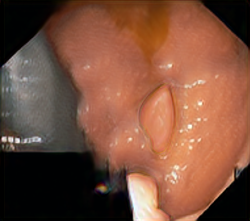

A few sample images and the corresponding masks of the polyp dataset in HyperKvasir are shown in Fig 2. The polyp images are RGB images. The masks of the polyp images are single-channel images with white () for true pixels, which represent polyp regions, and black () for false pixels, which represent clean colon or background regions. In this dataset, there are different sizes of polyps. The distribution of polyp sizes as a percentage of the full image size is presented in the histogram plot in Fig 3, and we can observe that there are more relatively small polyps compared to larger polyps. Additionally, a subset of this dataset was used to prove that the performance of segmentation models trained with small datasets can be improved using our SinGAN-Seg pipeline, and the whole dataset was used to show the effect of using SinGAN-Seg generated synthetic images instead of a large dataset which has enough data to train segmentation models. In this regard, this dataset was used for two purposes: